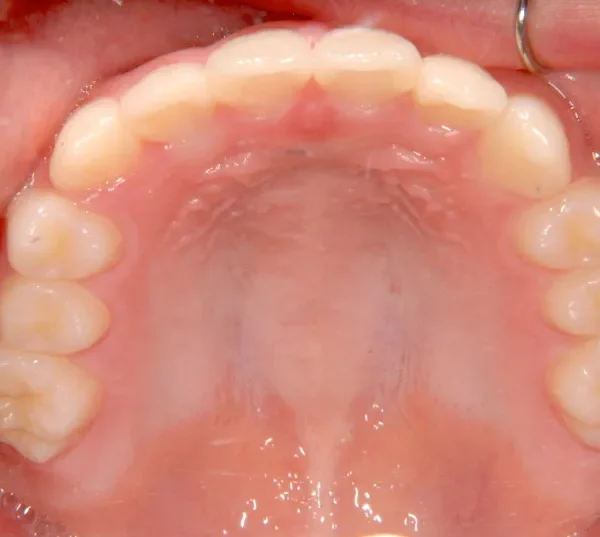

オリジナルの着け外しのできる装置で治療しました。

治療回数○回、4年7ヶ月の治療期間で矯正治療を終了しました。

1期治療で十分な結果が得られたと思います。

治療終了後